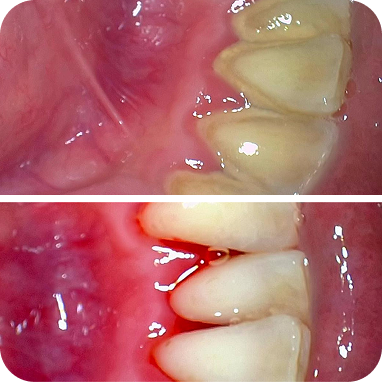

Karang gigi dibersihkan menyeluruh, termasuk area sulit dijangkau, sehingga gigi dan gusi tetap sehat lebih lama.

Di Dharmawangsa Dental Studio, scaling sudah termasuk polishing. Hasilnya lebih bersih menyeluruh, bukan sekadar karang gigi terangkat. Jangan tergiur harga murah di luar yang berakhir dengan biaya tambahan.